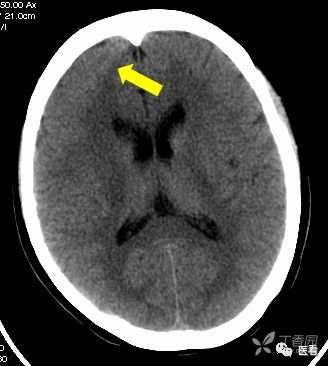

鸡冠 (红箭)所致放 射伪影 (黄箭)